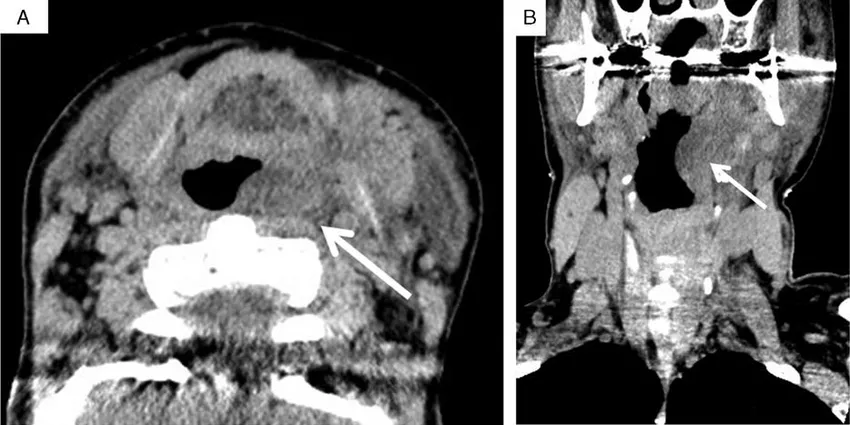

Рисунок 5. КТ шеи у пациента с наследственным ангиоотёком [6]. Стрелкой показано сдавление дыхательных путей (угроза асфиксии)